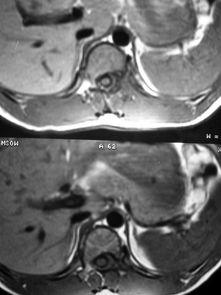

脊髓穿刺,听起来是不是有点吓人?其实,它是一种常见的医学检查方法,主要用于诊断脊髓病变、肿瘤、感染等疾病。通过视频,我们可以直观地看到手术的全过程,感受医生们的精湛技艺。

当一切准备就绪后,手术正式开始。医生会先在穿刺点处切开皮肤,然后用穿刺针穿过皮肤、肌肉层,直达脊髓。这一过程需要医生具备极高的精准度,因为一旦穿刺针偏离了方向,就可能造成严重的后果。

在手术过程中,医生会通过视频观察穿刺针的位置,确保其准确无误。同时,医生还会密切观察患者的反应,一旦发现异常情况,立即采取措施。